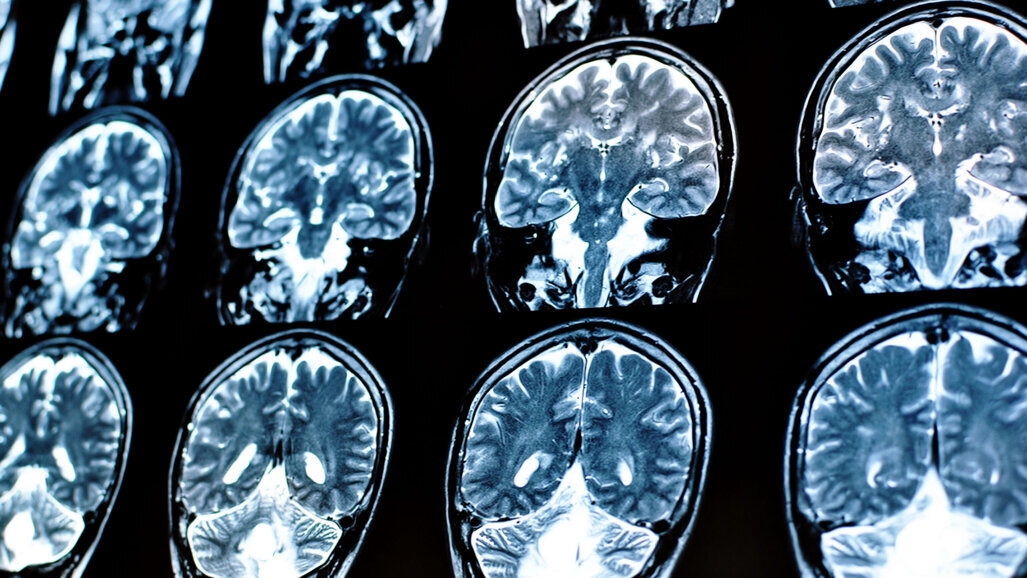

DALLAS, EUA: Um aumento da carga de doenças cerebrovasculares pode estar relacionado a uma predisposição genética para problemas de saúde bucal, de acordo com um novo estudo financiado pela American Heart Association. Os pesquisadores usaram a presença de hiperintensidades da substância branca, que são danos acumulados na substância branca do cérebro, como evidência de doença cerebrovascular. Documentados por meio de ressonância magnética (MRI), os exames resultantes mostraram que, para indivíduos geneticamente propensos ao edentulismo ou à cárie, houve um aumento de 24% nas hiperintensidades da substância branca em seus cérebros.

As hiperintensidades da substância branca estão ligadas a possíveis problemas de equilíbrio, mobilidade e memória. Os pesquisadores também geraram pontuações de dano microestrutural para os participantes. O dano microestrutural é o grau em que a fina arquitetura do cérebro mudou em comparação com as imagens de uma varredura cerebral normal de um adulto saudável de idade semelhante.

Usando dados do UK Biobank, as amostras incluíram indivíduos principalmente do Reino Unido de ascendência europeia. Eles foram avaliados para 105 possíveis variações genéticas ligadas à cárie, eventual necessidade de dentaduras ou qualquer forma de edentulismo. Os pesquisadores também observaram que, quando um participante tinha problemas de saúde bucal além de cárie e edentulismo como resultado da genética, a pontuação de dano microestrutural aumentava para 43%.

O principal autor, Dr. Cyprien Rivier, pesquisador de pós-doutorado no Departamento de Neurologia da Yale School of Medicine em New Haven, Connecticut, comentou em um comunicado à imprensa: “Estudar a saúde bucal é especialmente importante porque a má saúde bucal ocorre com frequência e é facilmente fator de risco modificável – todos podem efetivamente melhorar sua saúde bucal com o mínimo de tempo e investimento financeiro.” O Dr. Rivier também observou o valor do uso de ferramentas de neuroimagem, como a ressonância magnética, para avaliar o impacto da saúde bucal na função cerebral.

O Dr. Joseph P. Broderick, professor do Departamento de Neurologia e Medicina de Reabilitação da Universidade de Cincinnati e membro do Stroke Council, disse que as descobertas devem estimular mais pesquisas, mas não são evidências concretas de que uma melhor higiene bucal melhorará a saúde do cérebro. Ele observou que fatores genéticos para uma variedade de condições podem se sobrepor àqueles que causam problemas de saúde bucal. O Dr. Broderick disse: “Fatores ambientais, como tabagismo e problemas de saúde, como diabetes, são fatores de risco muito mais fortes para problemas de saúde bucal do que qualquer marcador genético - exceto para condições genéticas raras associadas a problemas de saúde bucal, como esmalte defeituoso ou ausente”.